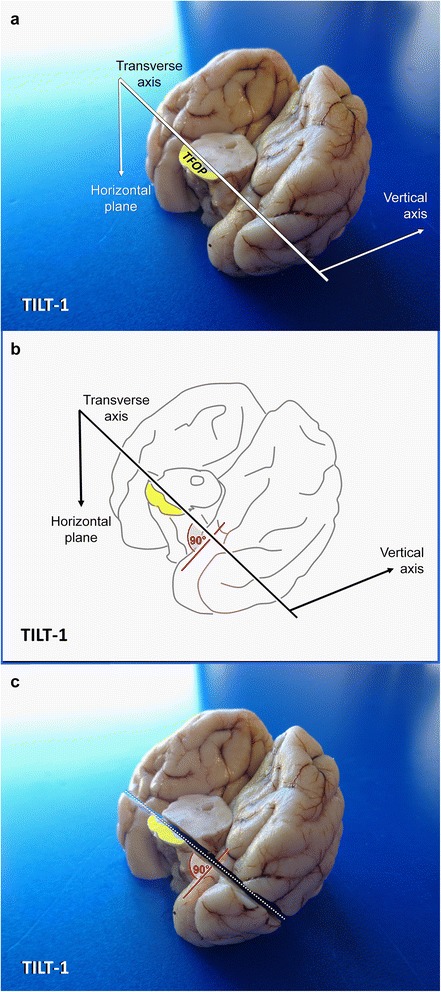

Fig. 6.

Planning of occipitotemporal brain dissection in three steps. TFOP: transverse fibres of pons; Aqu: mesencephalic aqueduct; PAG: periaqueductal gray matter. Canine brain

Dissection of the temporoventral body of the hippocampus via TILT-1 in a dog. MA: mesencephalic aqueduct PAG: periaqueductal grey matter; TFOP: transverse fibres of pons

Insert a long blade at the horizontal laterolateral axis (0° angle), where the TFOP border the tegmentum and lower the back edge of the blade ventrally until the sharp edge points towards the caudoventral curvature of the temporal lobes (caudal composite gyrus and base of piriform lobes) at a right angle (Fig. 7).

If you perform the section in this tilted caudoventral to rostrodorsal fashion (TILT-1), you will create a perpendicular section of the entorhinal cortex and TVB; differential evaluation of individual CA segments (e.g. for HS) or evaluation of the dentate gyrus and subiculum pathology will be easy and reliable.